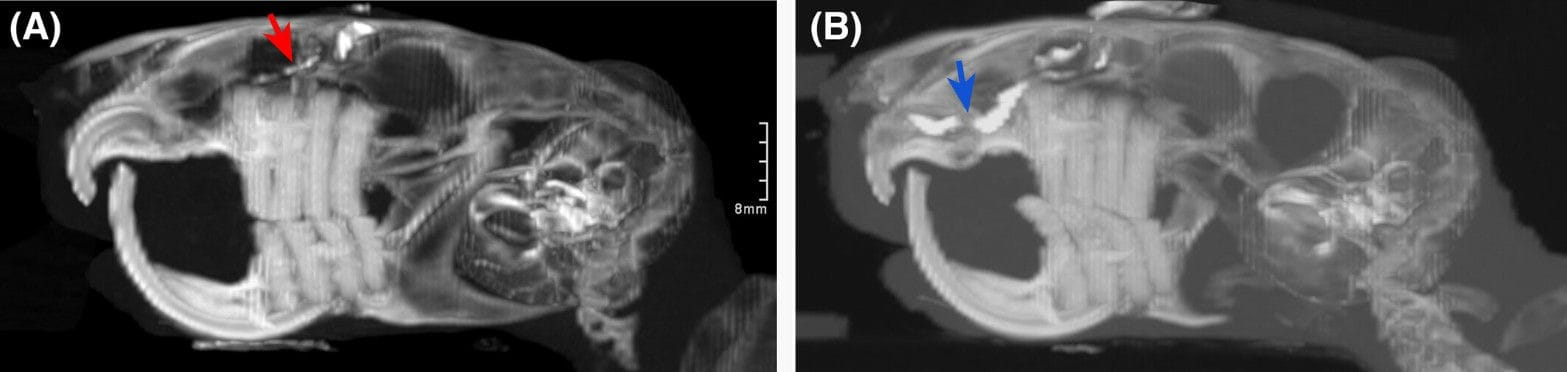

Contrast dacryocystorhinography of Chinchilla 2. The nasolacrimal punctum of the right eye could not be cannulated for contrast infusion (A). However, a small amount of contrast can be seen in the proximal duct (red arrow). Periapical abscessation of the retained left maxillary incisor extended into the nasal cavity and was associated with focal narrowing of the nasolacrimal duct (B), evident by the attenuation of the contrast column at this point (blue arrow) along with dilation of the nasolacrimal duct proximal to this point.